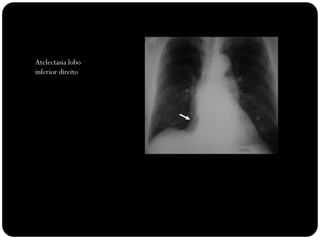

Atelectasia lobo

inferior direito

Observar:

Sinal de Luftsichel

Elevação

hemidiafrgma

esquerdo

Sinal da silhueta

(língula atelectasiada

também)